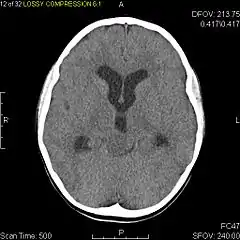

- Axial non-contrast CT in a nine-year-old girl showing a slightly hypodense mass in the tectum of the brainstem, compressing the aqueduct of Sylvius and causing obstructive hydrocephalus